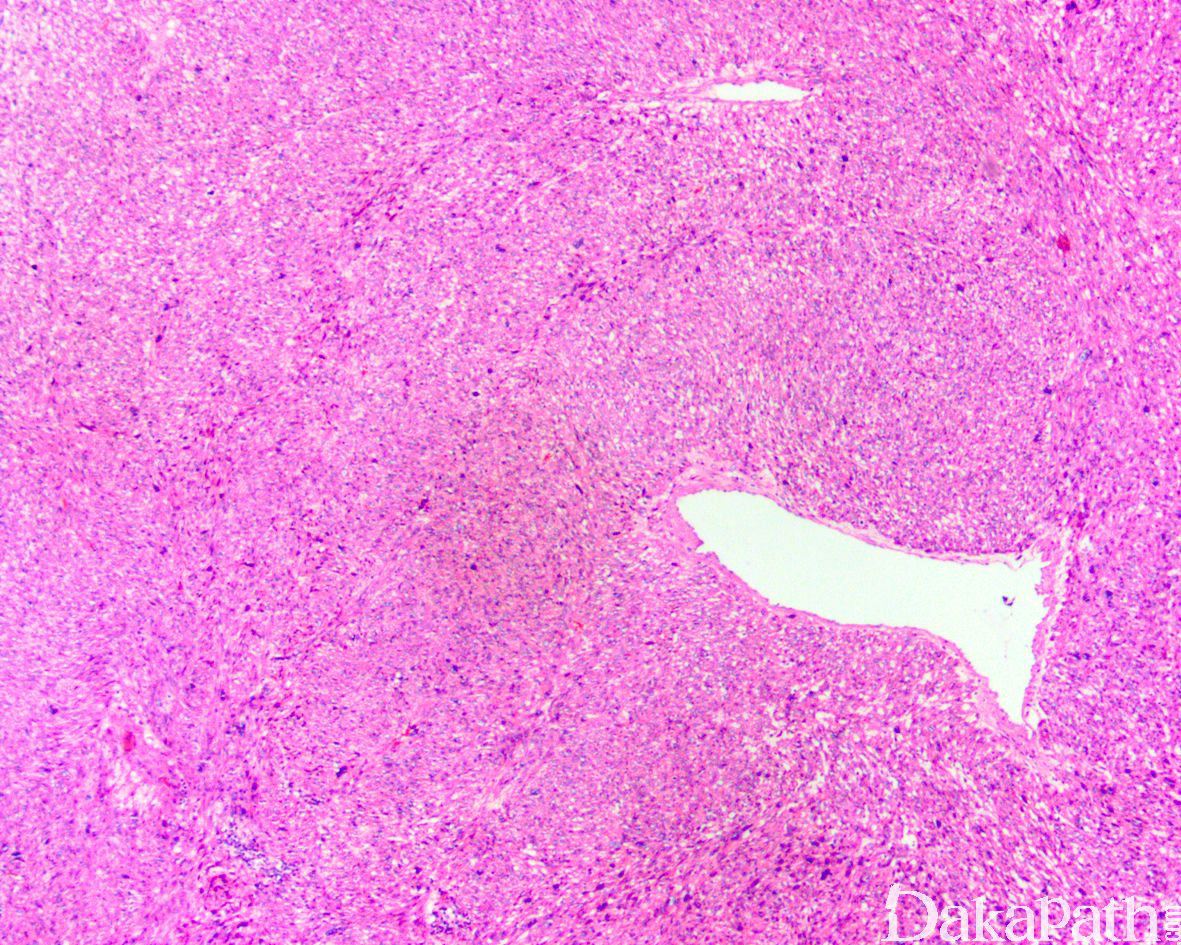

高分化及中分化平滑肌肉瘤:

主要由平行束状或编织排列的嗜伊红色梭形细胞组成;

瘤细胞的胞质丰富,深嗜伊红色,核居中,核两端平钝或呈雪茄样,局部区域可见散在核深染,形状不规则的瘤巨细胞;

部分瘤细胞核的一端可见空泡,常形成凹陷性压迹;

少数病例部分区域细胞核呈栅栏状排列,类似神经鞘瘤;

核分裂像多少不等,常 ≥5/10HPF,;

部分病例间质血管丰富,并常见瘤细胞围绕血管生长,呈血管外皮瘤样排列;

常见凝固性坏死;